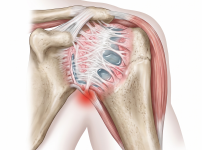

회전근개파열

오십견

석회성건염

어깨탈구

어깨관절염

상부관절와순파열